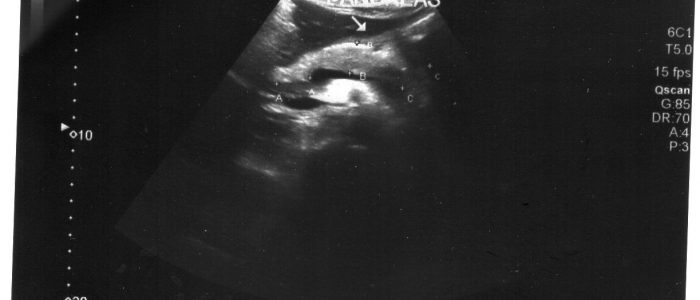

Выявить гемангиому селезенки можно после обследования на УЗИ или МРТ.

Выявить гемангиому несложно, она легко просматривается и на УЗИ и на МРТ, но часто остается скрытой, потому что имеет неярко выраженные симптомы и мало беспокоит больного. Если ее все-таки обнаружили, то чтобы подтвердить диагноз и выяснить вид новообразования, назначают ряд анализов, таких как анализ крови и костного мозга, биопсия, компьютерная томография. Ангиография — метод исследования, при котором в кровь вводится вещество, формирующее контрастное изображение на мониторе. Так можно получить самое четкое изображение новообразования и его строения.